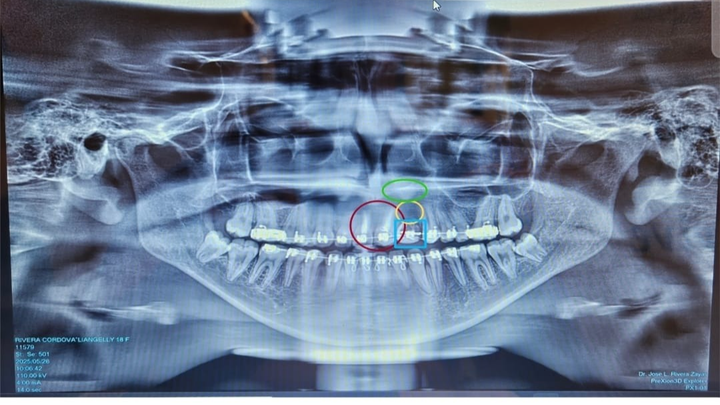

Hoy, con sus 18 años recién cumplidos, Liangelly finalmente puede someterse a los procedimientos médicos y dentales que necesita. Pero el tiempo ha pasado factura, y ahora enfrenta una serie de tratamientos complejos y costosos, incluyendo reconstrucción dental, injertos óseos y prótesis permanentes, además tiene un quiste y un abseso sobre un diente al cual se le realizó una biopsia y estamos en espera de los resultados.

Evaluaciones especializadas y radiografías 3D